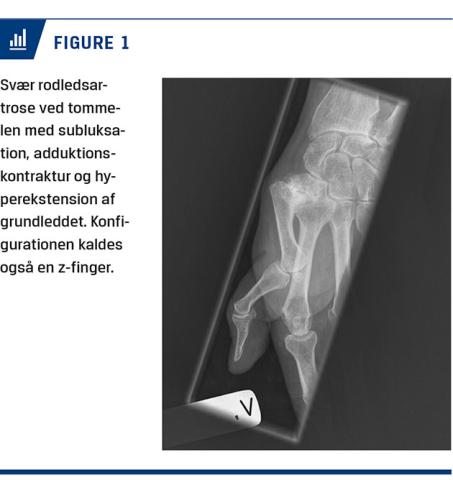

Diagnosen stilles klinisk på baggrund af en anamnese med typiske gener med belastningssmerter og senere hvilesmerter ved roden af tommelen. Objektivt findes der ofte hævelse af leddet og synlig subluksation. Der er ømhed ved palpation af leddet, og ofte kan man ved subluksation udløse smerter ved at trykke metacarpen ind på plads igen. Desuden udløses der tit smerter ved abduktion mod modstand og ved grinding test, hvor man roterer metacarpen under samtidig tryk proksimalt i længderetningen, ligesom der kan være krepitation i leddet ved bevægelse. I mere udtalte tilfælde kan der ses adduktionskontraktur af første metacarp med hyperekstension af grundleddet også kaldet z-deformitet (Figur 1).